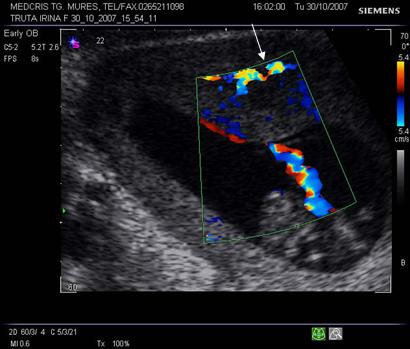

Mola invaziva se caracterizeaza printr-o crestere agresiva a trofoblastului in miometru.

Ecografia vaginala indica o structura hiperecogena miometriala in care apar zone bine definite hipoecogene reprezentand locul necrozei hemoragice.

Aspectul Doppler color este de flux sanguin puternic.

Fig. nr. 88.Ecografie transvaginala a molei invazive

Fig. nr. 89. Flux sangvin la Doppler , cu vascularizatie puternica , dupa chiuretajul molei invazive si persistente